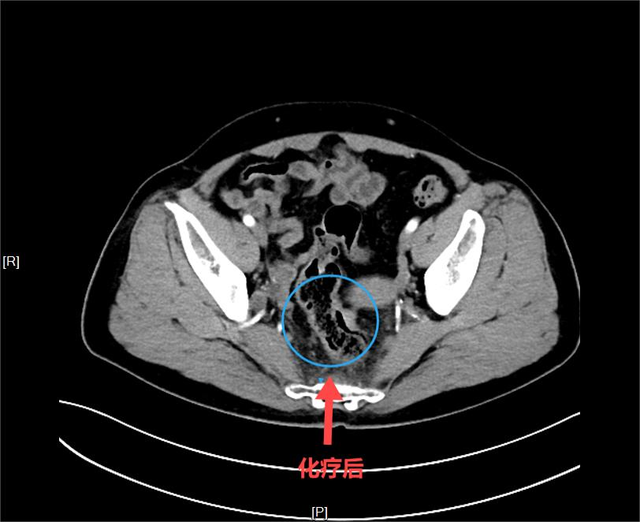

令人欣慰的是,经过四次两疗程的转化治疗后,刘阿姨明显感觉下腹部好像少了一样东西,身体轻松了好多。经过再次的增强CT评估,发现直肠肿瘤瘤体明显缩小,CT上几乎不可见,转移的淋巴结也明显缩小,显示出理想的治疗效果。

▲化疗后